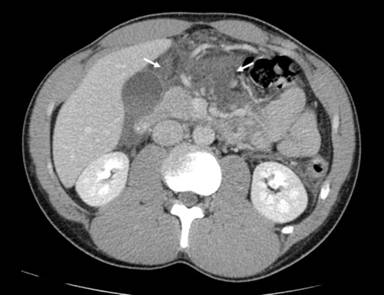

Computed tomography of abdomen and pelvis demonstrated a transection at the neck of the pancreas with large amounts of high attenuation free fluid and no other injuries (Figures 1 and 2). The patient was taken to the operating room for emergent laparotomy. Upon entering the abdomen, an extensive inflammatory and hemorrhagic reaction was encountered which encompassed the entire omentum and lesser sac, obscuring normal anatomy. It was deemed impossible to explore the site of injury through a direct anterior approach. Therefore the spleen and tail of the pancreas were mobilized anteromedially, exposing the site of transection to the left of the superior mesenteric vessels along with extensive devitalization of the distal remnant. The major pancreatic duct could not be visualized. Albumin-glutaraldehyde surgical adhesive (BioGlue®; Cryolife Inc., Kennesaw GA, USA) was applied to the cut surface of the proximal stump and distal pancreatectomy and splenectomy were completed. Two closed suction drains were placed.

Figure 2. Large amount of high attenuation fluid in the lesser sac and around the pancreas consistent with hemorrhagic reaction (arrows). |